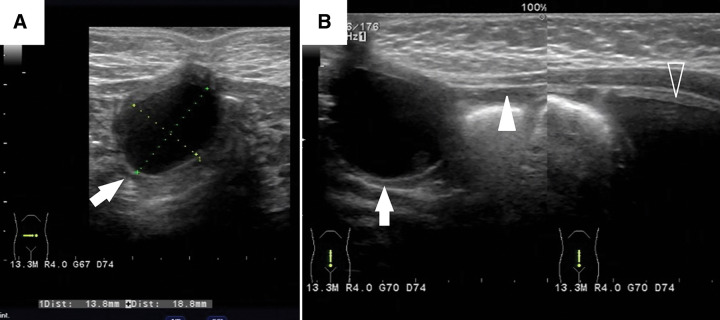

Case presentation: This study reports the case of a 17-day-old female infant who presented with a small moist umbilical nodule and a persistent yellowish mucinous discharge. Initial treatment for umbilical granuloma failed to resolve the lesion. Imaging revealed a 2-cm cyst beneath the umbilicus and a cord-like structure connecting it to the bladder. Surgical exploration identified a 6-cm fibrous band extending from the cyst to the ileal wall, consistent with an omphalomesenteric duct remnant, and a 5-mm diameter urachal remnant connecting the cyst to the bladder. Histological analysis confirmed the presence of intestinal mucosa and transitional epithelium. The postoperative recovery of the patient was without complications.